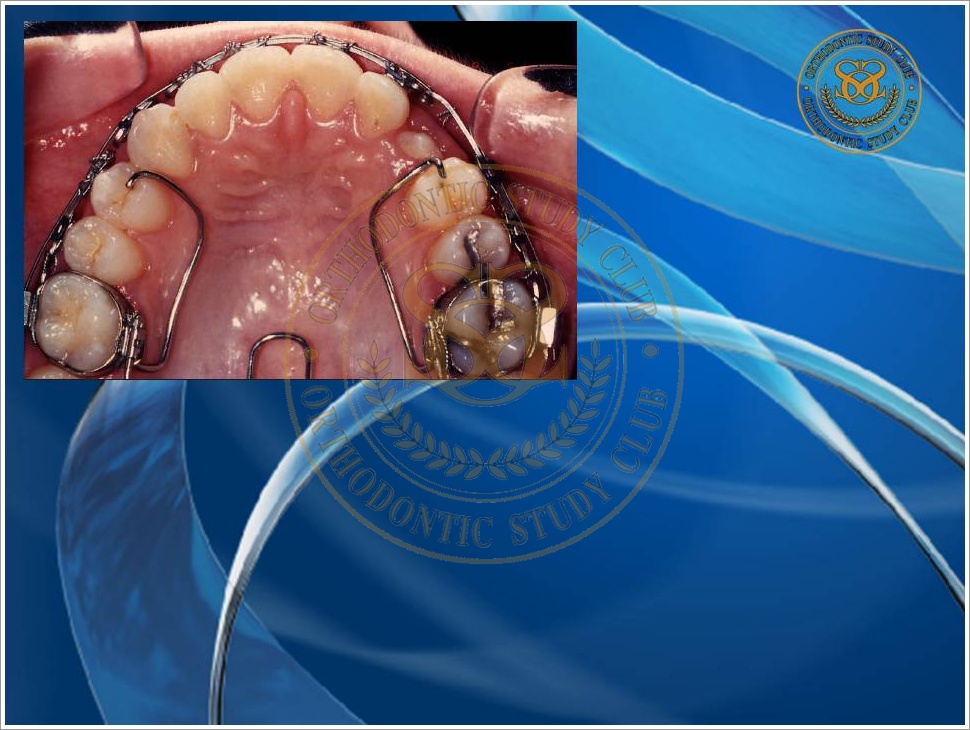

Treatment of Pseudo Class III (Class I Molar Relationship) and management of the embedded maxillary canine (Pt. Miss J.I.)